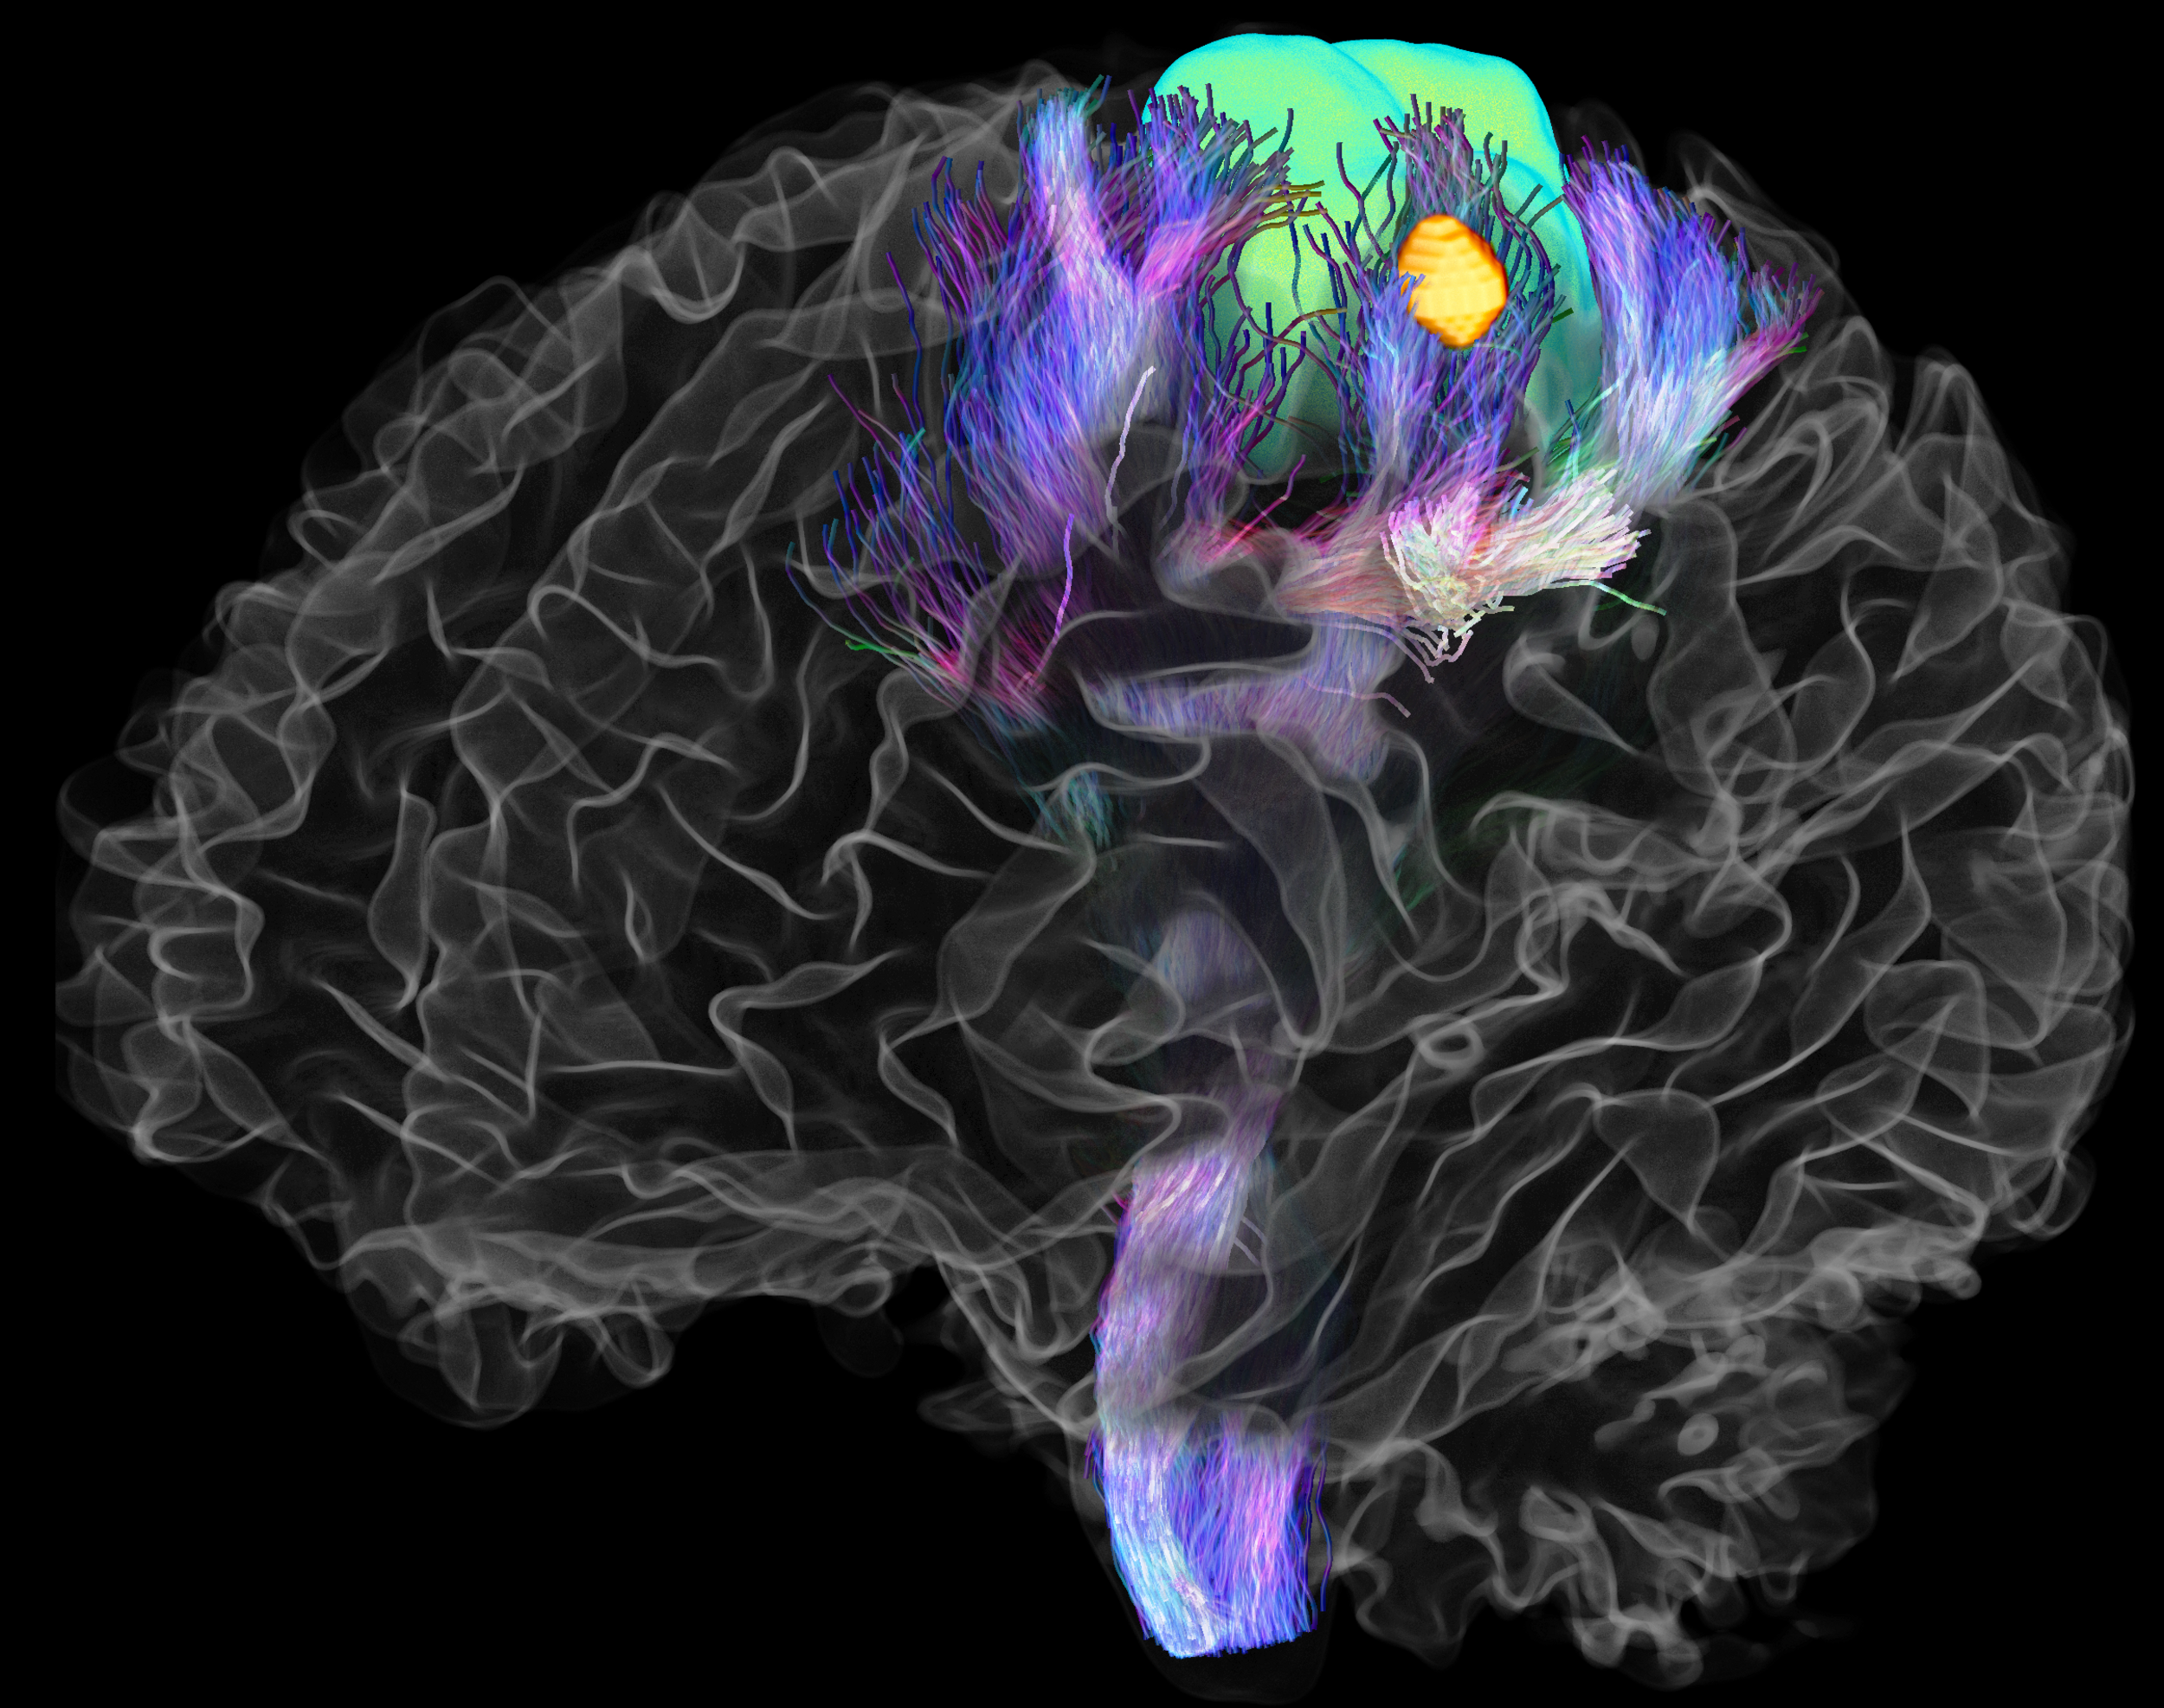

The Adaptive Digital Twin project aims to achieve their goals through four primary strategies. Firstly, we plan to implement a measure that allows real-time probing of effective local and widespread change in whole brain connectivity based on a combination of transcranial magnetic stimulation (TMS) and electroencephalography (EEG). Secondly, we generate high-quality neuroimaging data from brain tumor patients in a joined research project with DFG SPP 2041, which can be used to synthesize digital brain matter using machine-learning algorithms to dramatically increase cohort sizes. thirdly, we refine the correlation analyses of structure-function brain networks with psycholinguistic assessments and real-time mapping during awake surgery. Lastly, we model the effect of different lesions on the level of personalized biophysical brain network models by comparing patient profiles before and after their surgery along with their brain structure information.

In addition, in a further sub-project, we explore the material properties of the brain in relation to neuroimaging in tumor patients, investigating the effects of degeneration, pressure, or stretching mechanisms on brain tissues and the resulting functional consequences, in terms of network and behavior. We use MR-Elastography (MRE) imaging to measure local physical properties of brain matter and add a novel material science perspective to the question of the brain's structure-function relationship.